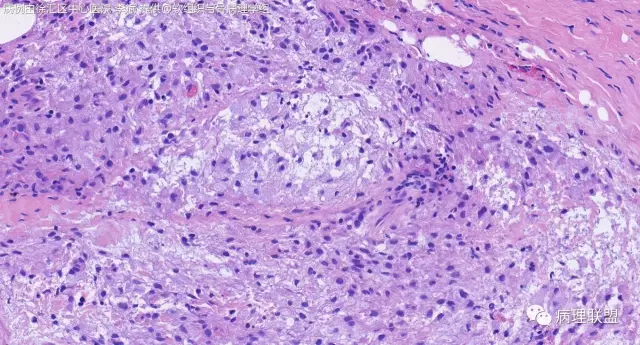

女,64岁,右腕部肿块,灰白不整形1*1*0.8cm(病例由徐汇区中心医院 李斌提供,致谢!)

神经鞘粘液瘤。

富于细胞神经鞘粘液瘤,s100阴。

关节旁粘液瘤,肿瘤中间明显有腱鞘囊肿结构,又发生在关节处!强烈提示为关节旁粘液瘤,部分病例可以呈分叶结构!平时多加观察腱鞘囊肿囊壁常可见粘液变性!范围一广就成粘液瘤样。

@周泉 周老师您好,李斌老师第一个病例里细胞都是上皮样的包浆宽的,嗜酸,粘液瘤细胞细胞梭的星形的,所以我考虑是神经鞘的了,您觉得粘液瘤细胞也可以这种形态吗?

@左淑英 部分应该是组织细胞